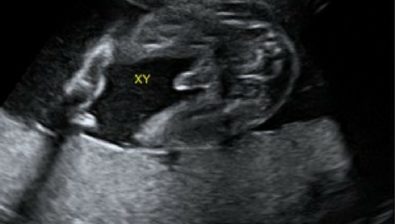

Ultrasound at 26 Weeks

Your baby is practice breathing more and more each day. He/she takes in gulps of amniotic fluid and then pees it back out.

This might sound a little gross, but this is just how babies let their organs “practice,” and it’s completely normal.

If you’re having a boy then his testicles have started to descend, but won’t be fully descended for another two to three months. If you’re having a girl, then she already has a lifetime supply of eggs already inside her.

26 weeks pregnant ultrasound #1 26 weeks pregnant ultrasound #2 26 weeks pregnant ultrasound #3 26 weeks pregnant ultrasound #4